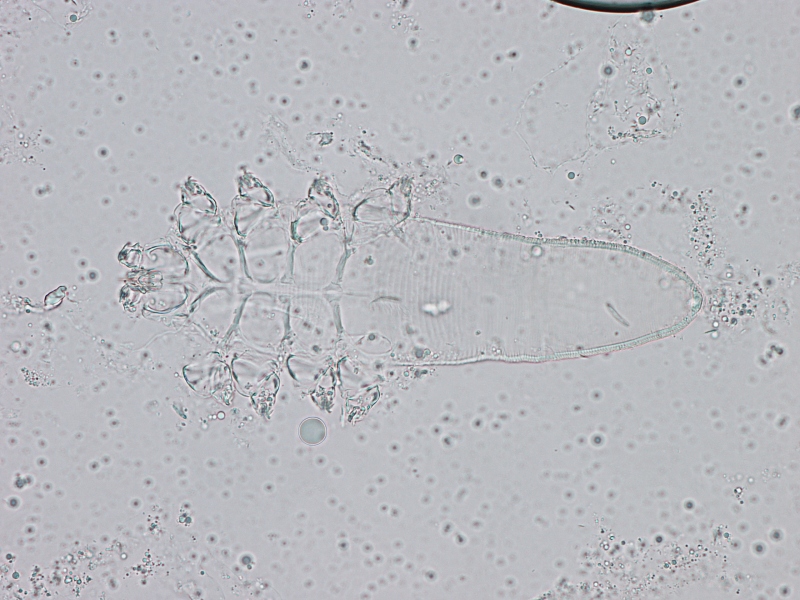

Souvent acarien sous-cutané Ce parasite affecte les chiens, mais aussi les chats. Ce satané parasite s'appelle Demodex.

Mais si le système immunitaire d'un chat s'affaiblit, ce parasite peut se manifester. Ces acariens (photo) infectent le plus souvent le contour des yeux, des oreilles et du cou. La perte de poils, les démangeaisons intenses et une peau rouge et enflammée sont des symptômes fréquents. Traiter un chat atteint de cette maladie est très difficile.